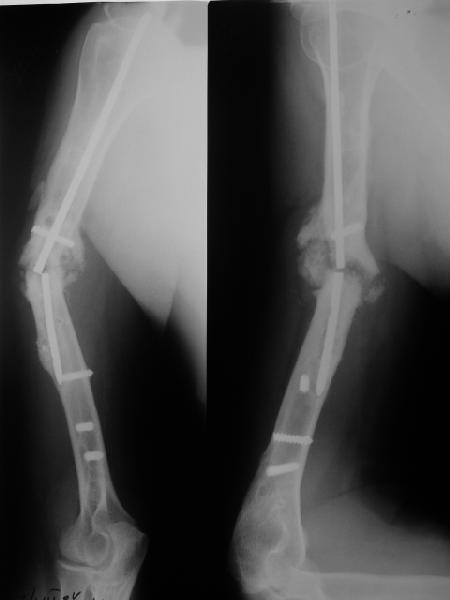

Такие надмыщелковые переломы в изолированном виде у нас в последние годы обычно фиксируются плоским титановым стержнем a la Зверев-Ключевский антеградно. Но тут еще и вышележащие проблемы.

Наверно, можно пойти на укорочение, убрав металлический цилиндр, не такой уж большой дефект. Снимки в чем-то похожего пациента прилагаю - тоже несращение диафиза после многократных операций, и надмыщелковый свежий перелом (случился после удаления обломка стержня аппарата).